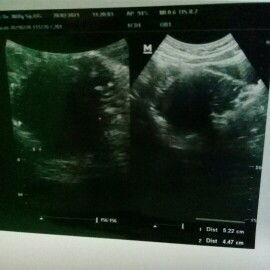

USG setelah keluar darah

Hasil USG hari ini bun. Sya positif hamil dan udh 2 hari saya keluar darah seperti haid. Apa ada yg tau ini hasilnya gmna ?#seriusnanya